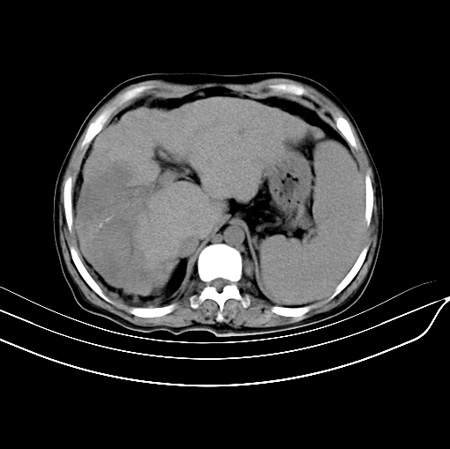

以下是引用江尾海头在2007-9-7 19:01:00的发言:[br]肝叶比例失调,肝边缘高低不平,尾状叶增大,肝裂增宽。肝右叶见较大密度减低影,边缘欠清。脾脏明显增大,胃底及奇静脉半奇静脉曲张。胆囊未见明显显示。 考虑:1、肝癌。2、肝硬化伴脾大静脉曲张。

以下是引用zhangxu5888在2007-9-7 22:31:00的发言:[br]1、肝硬化,食管 胃底及奇静脉半奇静脉曲张;2、脾脏肿大; 3、肝右叶的病灶呈锲性改变,内可见条片状钙化,边界清晰,密度明显低于周围正常肝组织,我觉得肝癌可能性不是很大, 同意楼上观点,有可能是栓塞,建议增强.

以下是引用余辉在2007-9-7 19:40:00的发言:[br]肝硬化也比较容易伴发脂肪肝,低密度区密度大体较均匀,且边界较清楚,也符合局灶性脂肪肝表现,不排肝癌,是要增强。